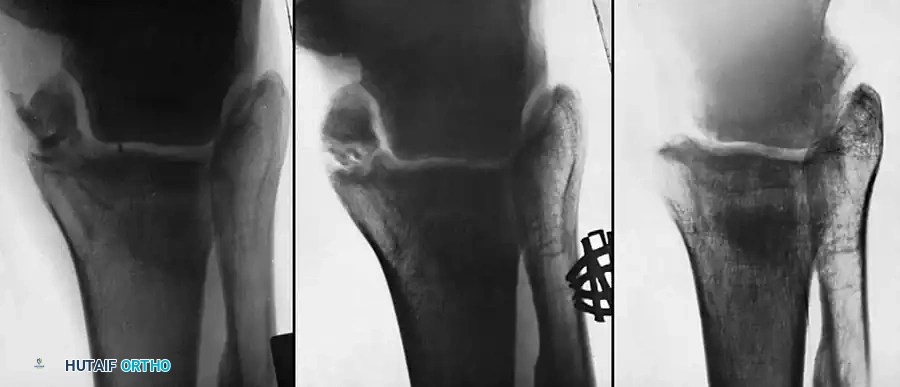

Medial Malleolus

A fracture of the medial malleolus occasionally fails to unite, especially after nonoperative (closed) treatment where periosteum or the deltoid ligament may interpose between the fracture fragments.

Surgery may be indicated for the few nonunions in which other serious complications of the fracture, such as advanced traumatic arthritis, are not seen on radiographs, and ideally if the injury is less than 2 years old. The standard surgical technique usually includes excision of the fibrous nonunion, application of autogenous bone grafts, and rigid internal fixation of the malleolar fragment.

When the nonunion is painful, it can be treated in one of three ways depending on the morphology of the fragment and the patient's functional demands:

- Bone Grafting and Fixation: When neither of the two previous treatments seems applicable (e.g., large fragment, young active patient, unstable mortise), formal bone grafting and internal fixation are indicated.